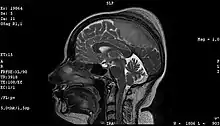

Meningioma of the middle third of the sagittal sinus with large hyperostosis

These common tumors can also be organized according to tissue of origin as shown below:[60]